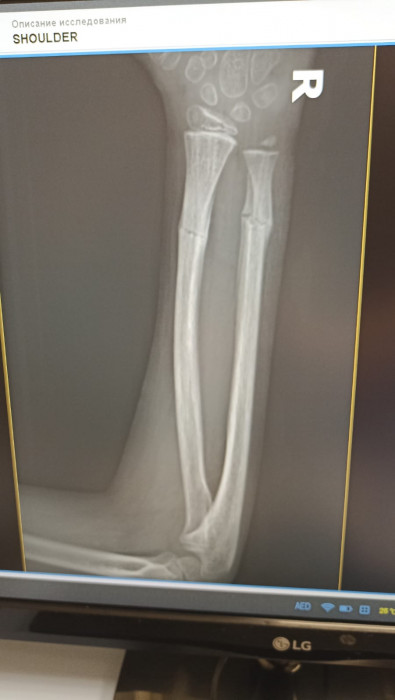

Кораблёв С.Г.: Да, вот ребёнок, 8 лет. Видно, перелом двух костей предплечья.

Кораблёв С.Г.: Адам, ещё раз: это второй снимок — боковая проекция. Это он на гипсе, это первичная репозиция, соответственно. И, вот, буквально они сделали на днях снимки, и всё прекрасно. Доктора сами удивились.

Кораблёв С.Г.: Две недели. Вот вы мне тогда дали рекомендации.

Кораблёв С.Г.: Я забыл сказать, что немного неправильно выбрали тип операции. Соответственно, здесь они поставили спицы, видите, но полностью сопостава не было. И там была еще ошибка, видимо, студенты удаляли, и после этого резко дёрнули, и перелом съехал в это положение. Это после операции. Они сказали: «Давайте подождем». И вот их выписали. Я смог забрать пациента себе, и вел на реабилитацию, поменял гипс, стянул, и мы каждый день работали-работали. И потом я с вашим методом познакомился.

Суриков В.П.: Настолько ровно получилось.

Кораблёв С.Г.: Ну вот факт, такой есть факт. То есть здесь не просто перелом, то есть еще спицы сделали, он ходил с ними, сняли, съехало, и угловая деформация еще больше стала. И сейчас уже такой результат.